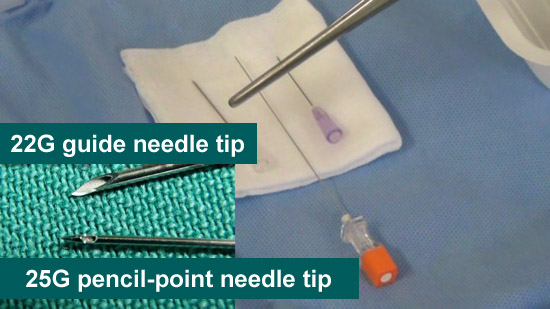

●Puncture needle

25-gauge pencil-point needle (Puncture needle)

22-gauge needle (Guide needle)

(3)Insert a guide needle (22-gauge needle) just in front of the dura mater

(4)Insert a pencil-point puncture needle into the dura mater